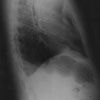

This patient had a sliding hiatal hernia. The double shadow in the right mid and lower lung field of the chest radiograph represents the herniated stomach, which contains gas (A, arrows).